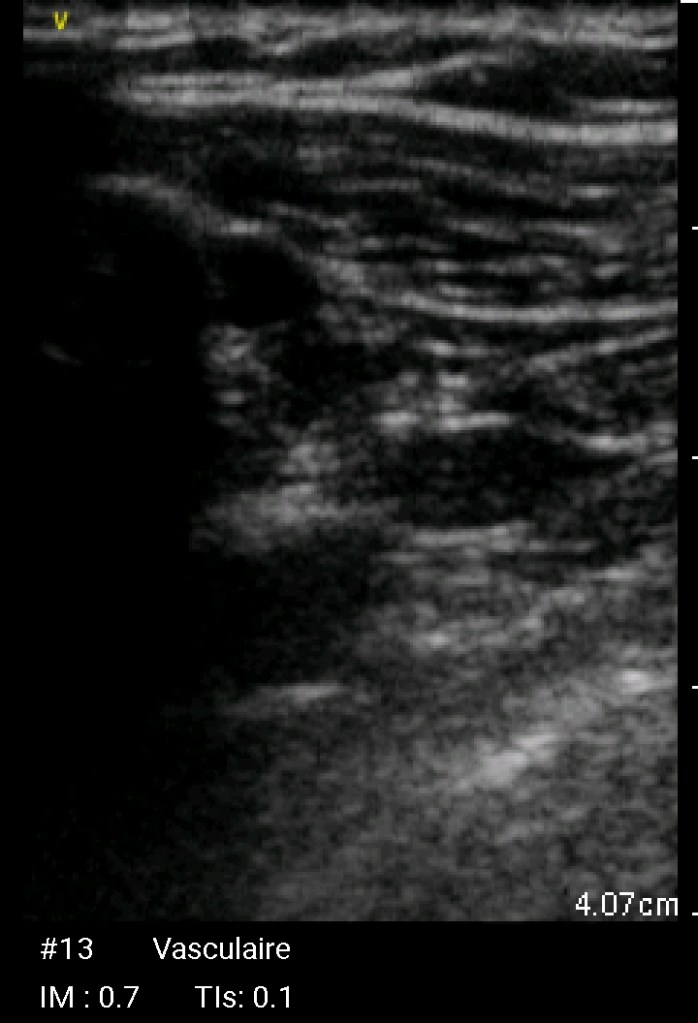

Echographie Sous-clavièreJugulaireFémorale JUGULAIRE G FEMORALE Dt MorissonKohlerDouglas Sous-clavièrePleural J’aime chargement…